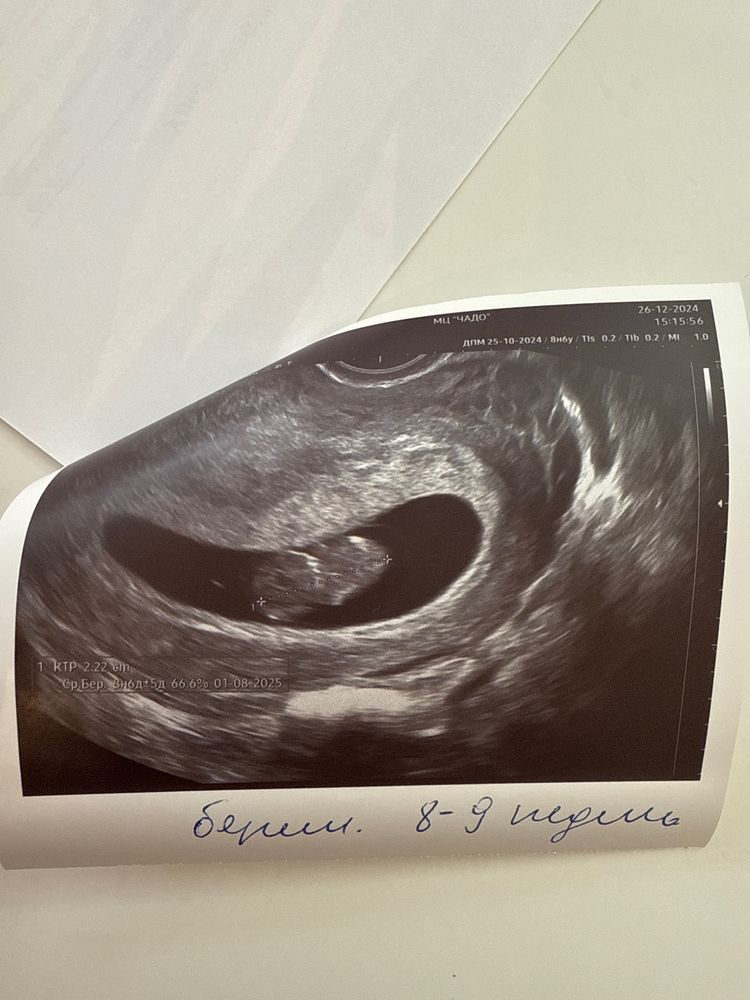

Узи в 9 недель

Всем привет)) токсикоз отпускает, чувствую себя уже человеком)) малыш растет, соответствует сроку) ктр 22,1 мм чсс 166 )) прикрепился по передней стенке и справа))) малыш во всю двигался)) это было прекрасно. 28 декабря встану на учет. Так интересно узнать кто у меня))) уже по всем приметам смотрела 🤣 так что 50 на 50 )) Как ваши дела?